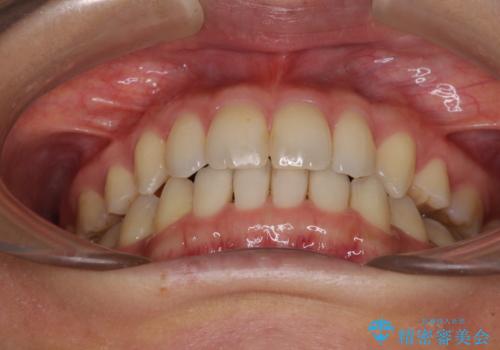

- 以前の矯正治療の後戻りにより、上の前歯にスペースができたことを気にして来院された患者様です。

インビザラインを用いて前歯のスペースを閉じつつ、上下の咬み合わせを構築していくこととしました。